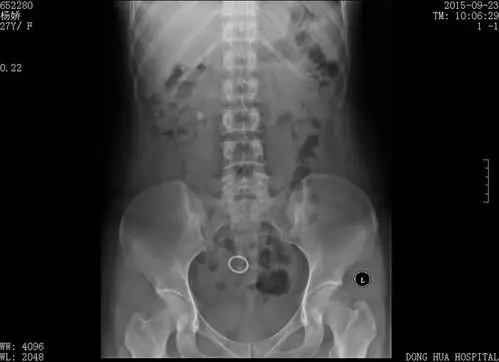

右输尿管上段结石治疗方法